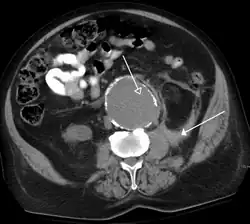

O scanare CT care prezintă anevrism de aortă abdominală ruptă | |